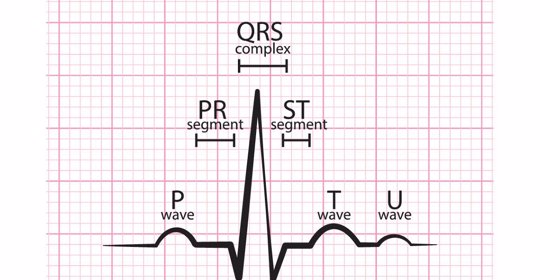

正常情況下兒童的心電圖與成人不同,因為兒童的胸腔較小且心臟也偏小。一般情況下,對於14歲以下的兒童而言,心電圖的標準數值如下:1.P波:在QRS波群之前出現,表示左房除極時,室內傳導柱從左向右移動引起心內膜和心外膜的浦肯野纖維快速去極擴散所致。

如果在孕期進行心電圖檢查提示正常結果,則無需擔心。但如果出現異常情況,如T波改變、ST段改變等,建議孕婦進一步完善相關檢查明確診斷,並遵醫囑治療。